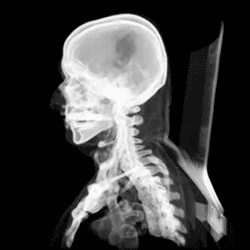

The skull, or cranium, is typically a bony enclosure around the brain of a vertebrate.[1][2] In some fish, and amphibians, the skull is of cartilage. The skull is at the head end of the vertebrate.

In the human, the skull comprises two prominent parts: the neurocranium and the facial skeleton,[3] which evolved from the first pharyngeal arch. The skull forms the frontmost portion of the axial skeleton and is a product of cephalization and vesicular enlargement of the brain, with several special senses structures such as the eyes, ears, nose, tongue and, in fish, specialized tactile organs such as barbels near the mouth.[4]

The skull is composed of three types of bone: cranial bones, facial bones and ossicles, which is made up of a number of fused flat and irregular bones. The cranial bones are joined at firm fibrous junctions called sutures and contains many foramina, fossae, processes, and sinuses. In zoology, the openings in the skull are called fenestrae, the most prominent of which is the foramen magnum, where the brainstem goes through to join the spinal cord.

The human skull is the bone structure that forms the head in the human skeleton. It supports the structures of the face and forms a cavity for the brain. Like the skulls of other vertebrates, it protects the brain from injury.[6]

The skull consists of three parts, of different embryological origin—the neurocranium, the sutures, and the facial skeleton. The neurocranium (or braincase) forms the protective cranial cavity that surrounds and houses the brain and brainstem.[7] The upper areas of the cranial bones form the calvaria (skullcap). The facial skeleton (membranous viscerocranium) is formed by the bones supporting the face, and includes the mandible.